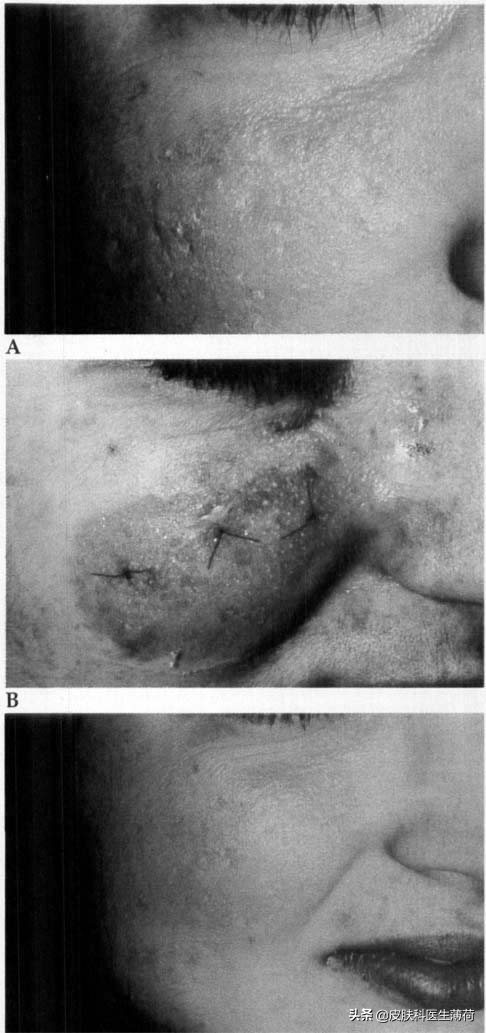

事实上,每个坑是不一样的!都有自己的“个性”!虽然每个坑都长得不尽相同,但总体而言,可以将痘坑可以分为以下几类:

1. 冰锥样:范围<2mm,但深度直达真皮组织

点评:是“坑中之王”!虽然看起来小,但又尖又深!远看容易跟粗大的毛孔混淆。

处理方法:环转抬高术、TCA深层换肤、激光皮肤磨削术、射频。

2. 滚轮样:4-5mm大小,边缘是圆圆的

点评:更容易形成“凹凸不平”的感觉,相对好处理,特点是比较大只,通常比较表浅。

处理方法:环转切除术、皮下填充术、微针、激光皮肤磨削术、射频、皮肤磨削术。

3.厢车样:1.5-4mm大小,边缘陡峭

点评:可深可浅、可大可小,像一个个正正方方的坑。

处理方法:环转切除术、皮下填充术、微针、激光皮肤磨削术、TCA深层换肤、射频、皮肤磨削术。

环转抬高术是使用一次性活检器,将局部的凹陷组织与周围组织分离,并让它抬高与周围的皮肤组织相平,如果取的组织比较大,还需要进行手术缝合,适合浅、深厢车样疤痕。

环转切除术与抬高术类似,但多了一个将组织切除后缝合的步骤,适合冰锥样、深厢车样疤痕。通常术后修复期更长,可能会遗留线状的疤痕。